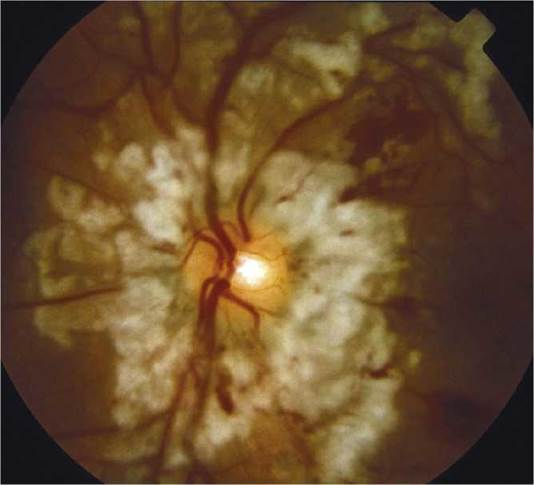

(See Figure 3.1.1.)

FIGURE 3.1.1 Alkali burn.

Critical. Pronounced chemosis and conjunctival blanching, corneal edema and opacification, a moderate to severe AC reaction (may not be appreciated if the cornea is opaque).

Other. Increased IOP, second- and third-degree burns of the surrounding skin, and local necrotic retinopathy as a result of direct penetration of alkali through the sclera.